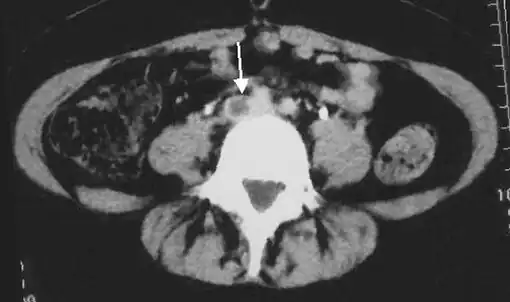

Deep vein thrombosis (DVT) is a type of venous thrombosis involving the formation of a blood clot in a deep vein, most commonly in the legs or pelvis.[9][lower-alpha 1] A minority of DVTs occur in the arms.[11] Symptoms can include pain, swelling, redness, and enlarged veins in the affected area, but some DVTs have no symptoms.[1] The most common life-threatening concern with DVT is the potential for a clot to embolize (detach from the veins), travel as an embolus through the right side of the heart, and become lodged in a pulmonary artery that supplies blood to the lungs. This is called a pulmonary embolism (PE). DVT and PE comprise the cardiovascular disease of venous thromboembolism (VTE).[2] About two-thirds of VTE manifests as DVT only, with one-third manifesting as PE with or without DVT.[12] The most frequent long-term DVT complication is post-thrombotic syndrome, which can cause pain, swelling, a sensation of heaviness, itching, and in severe cases, ulcers.[5] Recurrent VTE occurs in about 30% of those in the ten years following an initial VTE.[3]

A pulmonary embolism (PE) occurs when a blood clot from a deep vein (a DVT) detaches from a vein (embolizes), travels through the right side of the heart, and becomes lodged as an embolus in a pulmonary artery that supplies deoxygenated blood to the lungs for oxygenation.[28] Up to one-fourth of PE cases are thought to result in sudden death.[12] When not fatal, PE can cause symptoms such as sudden onset shortness of breath or chest pain, coughing up blood (hemoptysis), and fainting (syncope).[29][30] The chest pain can be pleuritic (worsened by deep breaths)[29] and can vary based upon where the embolus is lodged in the lungs. An estimated 30–50% of those with PE have detectable DVT by compression ultrasound.[30]